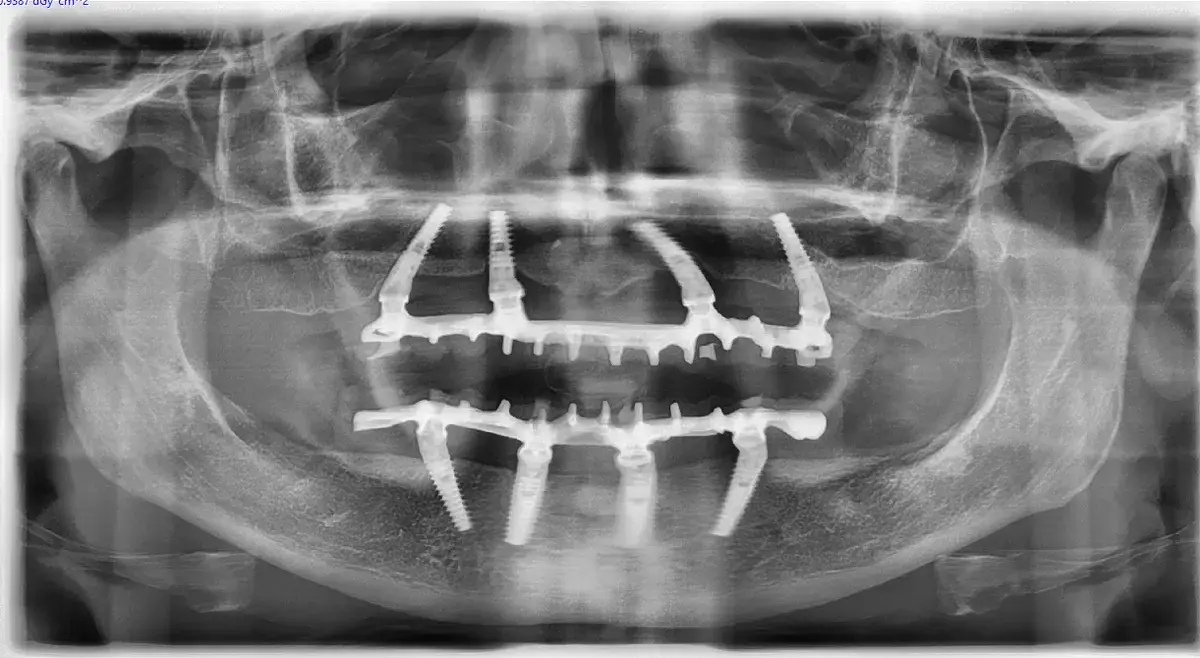

Gli impianti Kalodon, in particolare i Newton e i Zerocompromise, vogliono guidare la guarigione ossea con un abile intreccio tra contatto e “non-contatto” osseo. Le spire aggressive sono in diretto contatto con l’osteotomia e creano un forte legame per la stabilità primaria, mentre le zone di non contatto, rappresentate dai solchi a doppia elica (come il DNA) che si approfondiscono verso il centro delle fixture e favoriscono l’osteogenesi a distanza, descritta da Davies dell’università di Toronto. Il giusto equilibrio tra osteogenesi a distanza e osteogenesi da contatto consente di ottenere una grande stabilità iniziale, che consente il carico immediato e, nel contempo, un rapida ossificazione delle zone inizialmente vuote che impediscono lo slittamento dell’impianto durante le manovre protesiche, come spesso avviene con gli impianti troppo “lisci”.

La nostra idea è che l’osteogenesi a distanza, favorita da fosse e solchi profondi che intersecano le doppie spire aggressive e che un amico caro chiama “camere di coagulo” (perché questo sono), rappresentano un ausilio fondamentale nella moderna implantologia e ancor più nell’implantologia rigenerativa.

Che differenza c’è tra osteogenesi da contatto e osteogenesi a distanza? L’osteogenesi da contatto avviene dove l’impianto tocca l’osso (spire aggressive). L’osteogenesi a distanza avviene nei “vuoti” creati dai solchi profondi, dove il sangue si coagula e le cellule colonizzano il sito dai bordi. I due meccanismi insieme garantiscono ossificazione rapida e completa.

I solchi profondi e le “camere di coagulo” sono veramente necessari? Sì. Le camere di coagulo facilitano la formazione del coagulo di fibrina che serve da matrice biologica naturale per la rigenerazione ossea. Questo è il motivo per cui design con solchi profondi mostrano risultati superiori nella pratica clinica.